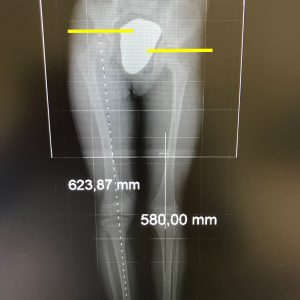

dismetría